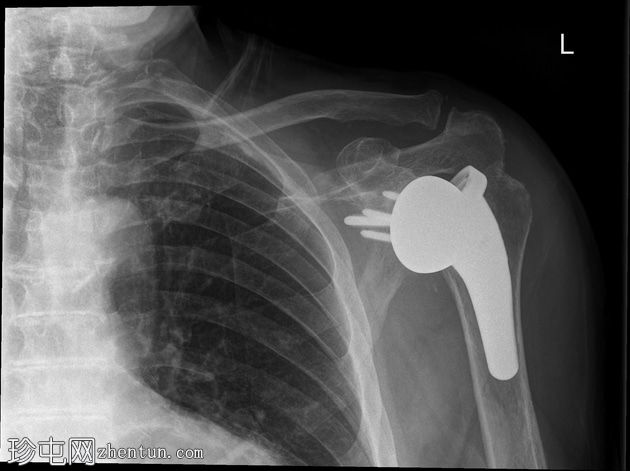

X光片

侧面

反式全肩关节置换术后肱骨假体前脱位。无假体周围透亮区或骨折。

反式全肩关节置换术后早期(90天内)脱位是已知但并不常见的并发症。多种患者、手术和植入物因素都可能与此相关,但在本例中,除了男性因素外,尚无其他明确的原因。